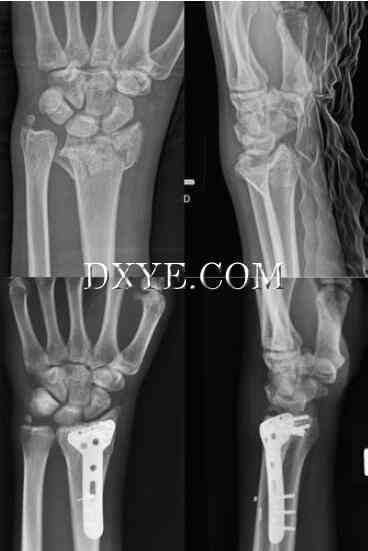

三影像学测量标准的PA和侧视图与患者的预后相关:径向高度、径向倾斜,和掌倾角(图76.5)。桡骨高度在PA片作为一个垂直的半径通过乙状切迹远端的尺骨远端关节面半径的长轴在桡骨茎突尖第二垂直线之间的距离测量。正常径向高度平均为10至14毫米。桡骨关节面有桡尺坡(径向倾角)和背向掌侧坡(掌侧倾斜)。

在PA射线照片上也测量径向倾斜,并且表示连接桡骨茎突的尖端和远侧半径的尺骨方向的一条线与垂直于半径的纵向轴线的第二线之间的角度。 正常的径向倾角在20°和25°之间。 手掌倾斜度是在侧位X线片上测量的,代表了沿着半径的远端关节面的线与垂直于半径的纵轴线的线之间的角度。 正常手掌倾斜平均11°,范围5°至15°。 有用的附加射线照相参数是尺骨方差。 尺骨方差是指尺骨头的关节面与月骨的尺骨边界之间的距离。 当两者都处于同一水平时,它被描述为中性:尺骨加上尺骨长的时候; 和尺骨减去尺骨短的时候(图76.6)。 正常尺骨方差的范围可以从0±2毫米。

图 76.5.  桡骨远端[径向高度的影像学参数测量(红色虚线),径向倾角(白色虚线),和掌倾角(绿色虚线)]。